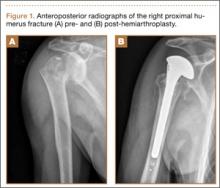

Overnight the patient’s mental status began to deteriorate, and approximately 10 hours after initial assessment, he was not answering questions but was able to respond to some commands. On hospital day 2, approximately 20 hours after initial assessment, the patient had a GCS of 8, was not responding to commands, and moved only in response to painful stimuli. The patient had been prescribed morphine by patient-controlled analgesia and had received intravenous hydromorphone on the day of admission, although the amount of medication delivered was not thought adequate to explain this deterioration. On the morning of hospital day 2, noncontrast brain computed tomography (CT) was normal with no evidence of intracranial hemorrhage or infarct. This was followed by brain magnetic resonance imaging (MRI), with the T2-weighted images showing numerous, small hyperintense lesions in subcortical and periventricular white matter, corpus callosum, basal ganglia, brain stem, and cerebellar hemispheres (Figure 2). The lesions also showed hyperintensity on diffusion-weighted MRI and were interpreted to be consistent with multiple, tiny infarcts (Figure 3). In addition, susceptibility-weighted sequences showed low signal in the same areas, suggesting multiple microhemorrhages, a pattern consistent with FES. Oxygen saturations remained 95% to 99%, and chest radiograph revealed clear lung fields without infiltrate. On hospital day 2, the patient was transferred to the intensive care unit and intubated for airway protection owing to an inability to clear secretions, although arterial blood gas levels remained normal. An echocardiogram revealed no right-to-left shunt, such as a patent foramen ovale (PFO); an electroencephalogram showed no seizure-like activity. No petechial rash was noted on skin examination. The patient was treated with supportive care. Right shoulder hemiarthroplasty was performed on hospital day 7 without complications (Figure 1). On hospital day 13, the patient was following commands and on day 14 he was extubated. His mental status continued to improve, and he was discharged to a rehabilitation facility after 36 days. On last follow-up, 6 months after initial injury, the patient was recovering well with no residual neurologic deficits and only minor limitation in range of motion of the right shoulder.